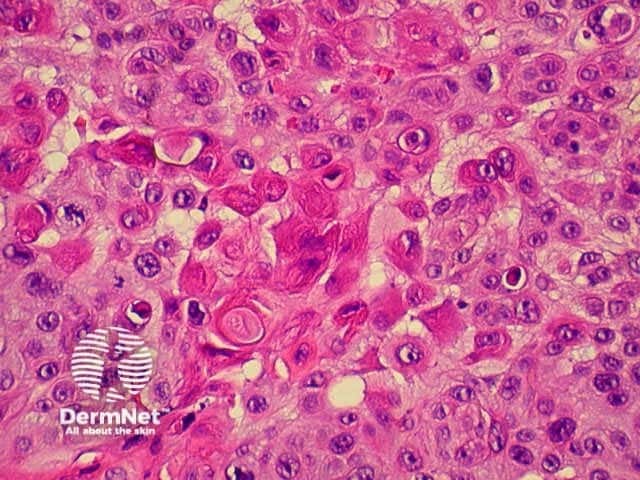

The histological characteristics of keratinocytic tumours are illustrated below.

Squamous cell carcinoma